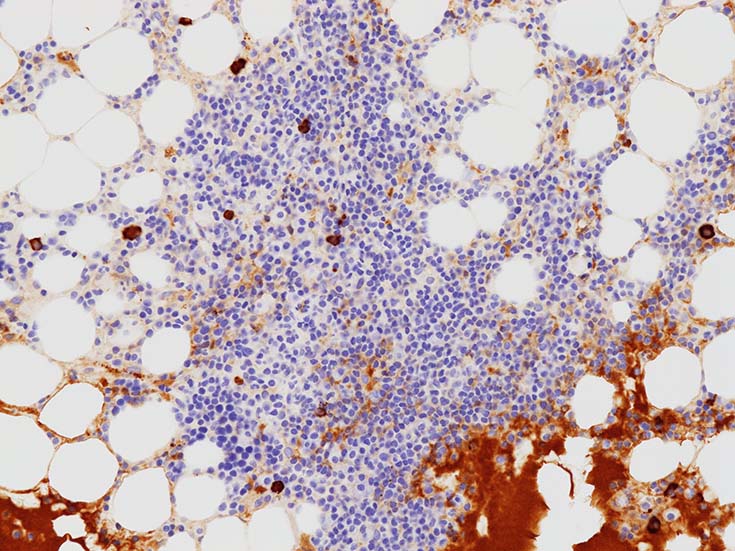

mast cellsは周辺部に出現することが多いようである.多発性骨髄腫の結節にはmast cell増加を認めることは経験上ない.

CD138陽性形質細胞の分布. 中央部よりも周辺部に陽性細胞が多くみられる.